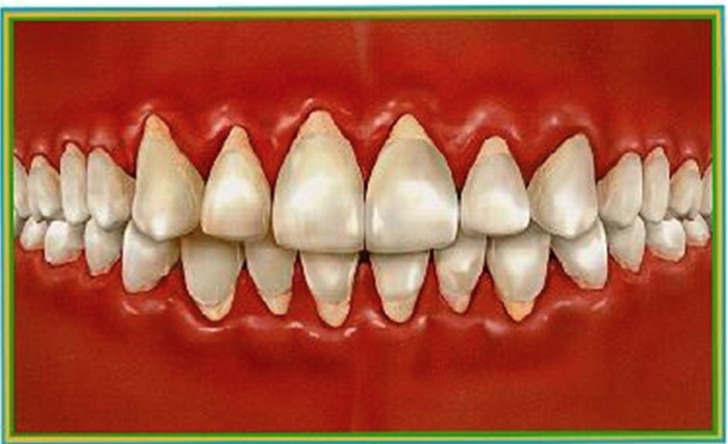

localized juvenille perio

localized juvenile perio